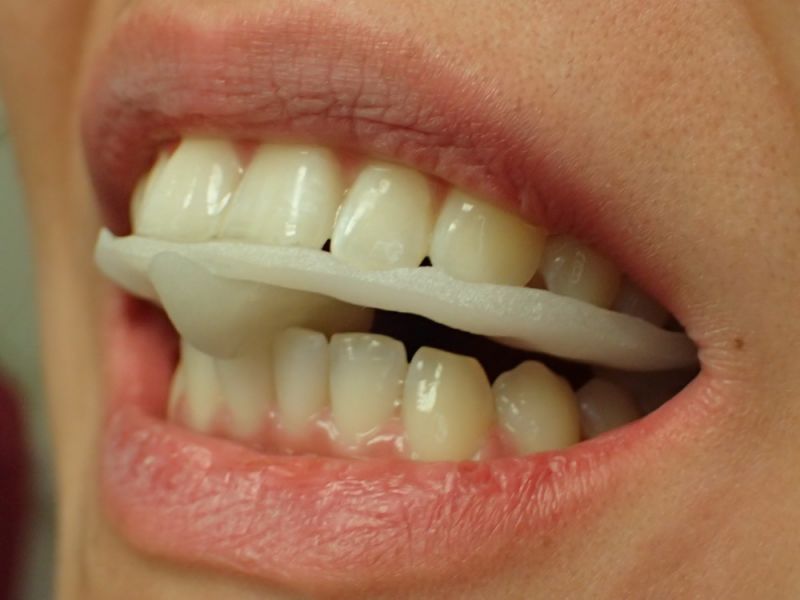

Es erfolgen die Maßnahmen der funktionellen Erstuntersuchung und die Herstellung und Eingliederung eines adjustierten Aufbissbehelfs zum Nachweis einer CMD.

Es erfolgen die Maßnahmen der klinisch manuellen Erstuntersuchung und nachfolgend die Maßnahmen zu Herstellung und Eingliederung eines adjustierten Aufbissbehelfs